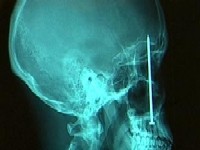

čavel v glavi vsi imamo...

Patrick Lawler iz Colorada otišao je k zubaru zbog jake zubobolje, no rendgenom je utvrđeno da uzrok boli nije pokvareni zub, nego čavao u glavi dugačak 10 centimetara. Bol je osjećao otkako je na poslu pogođen u glavu iz pištolja za čavle. Čavao mu se zabio četiri centimetra u mozak, nadomak lijevom oku, a odstranjen je četverosatnom operacijom. |